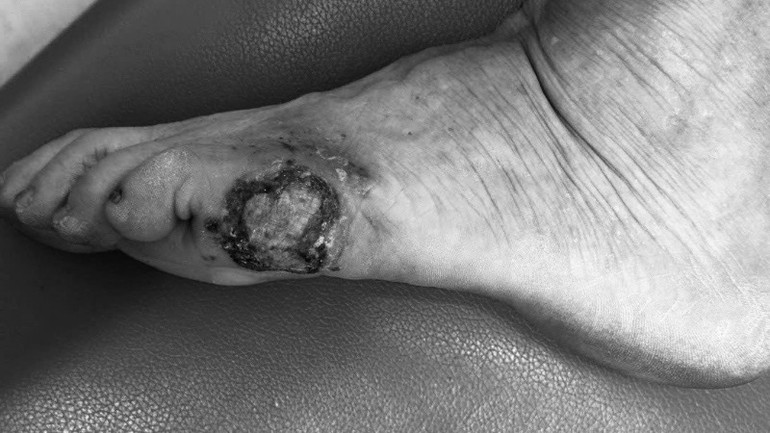

Qua thăm khám, bác sĩ Vũ Nguyên Bình, Khoa Phẫu thuật tạo hình thẩm mỹ và phục hồi chức năng, Bệnh viện Da liễu Trung ương đánh giá bệnh nhân tỉnh táo, không sốt, toàn trạng ổn định, tổn thương chính là mảng tăng sắc tố vùng bờ ngoài bàn chân trái, kích thước 4x3cm, ranh giới tương đối rõ so với da lành xung quanh, bờ không đều, bề mặt đóng vảy tiết bẩn. Bệnh nhân cũng mắc một số bệnh như tăng huyết áp, sỏi thận…

| Hình ảnh tổn thương của bệnh nhân. |